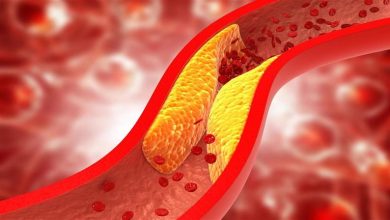

لا تدع غذائك يدمر قلبك.. 5 أطعمة شائعة تسبب أمراض القلب والس

02:32 م السبت 17 أغسطس 2024 كتبت- أسماء العمدة: تُعد أمراض القلب من بين أكثر مسببات الوفاة شيوعًا على مستوى…

على الريق.. 4 أطعمة تحارب الكوليسترول و3 ترفعه في الحال

تساعد بعض الأطعمة عند تناولها على الريق في خفض مستوى الكوليسترول، مما يمكن أن يكون بداية جيدة ليوم صحي. تقول…